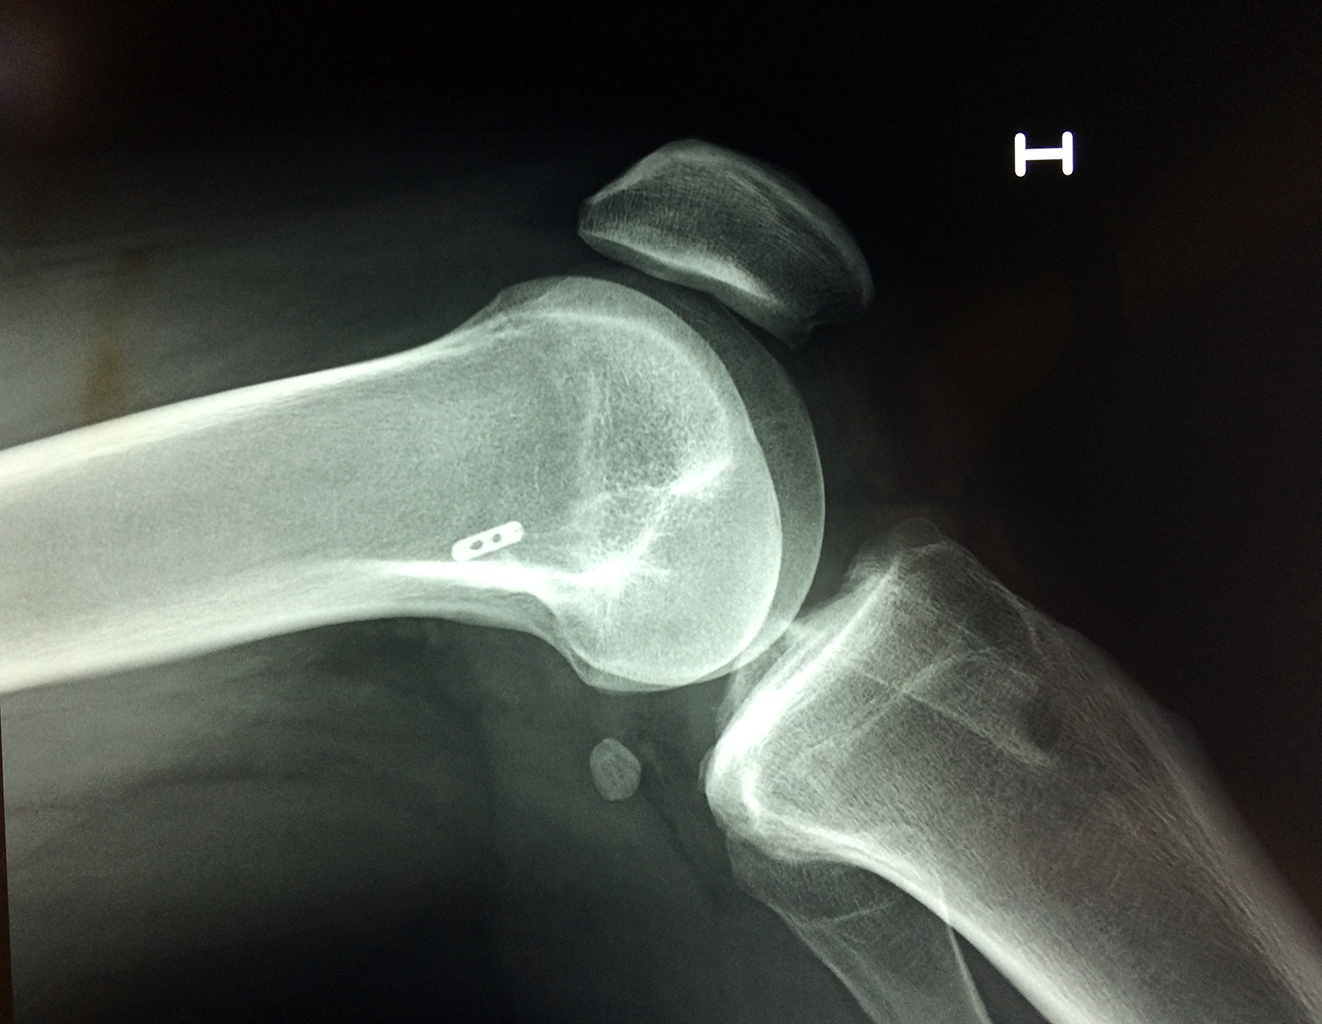

Fémur - Rodilla

La artroscopia de rodilla es un cirugía en el cual la estructura interna de la articulación es examinada ya sea para realizar un diagnostico o para realizar un tratamiento, este procedimiento se realiza utilizando un instrumento parecido a un pequeño tubo llamado artroscopio.